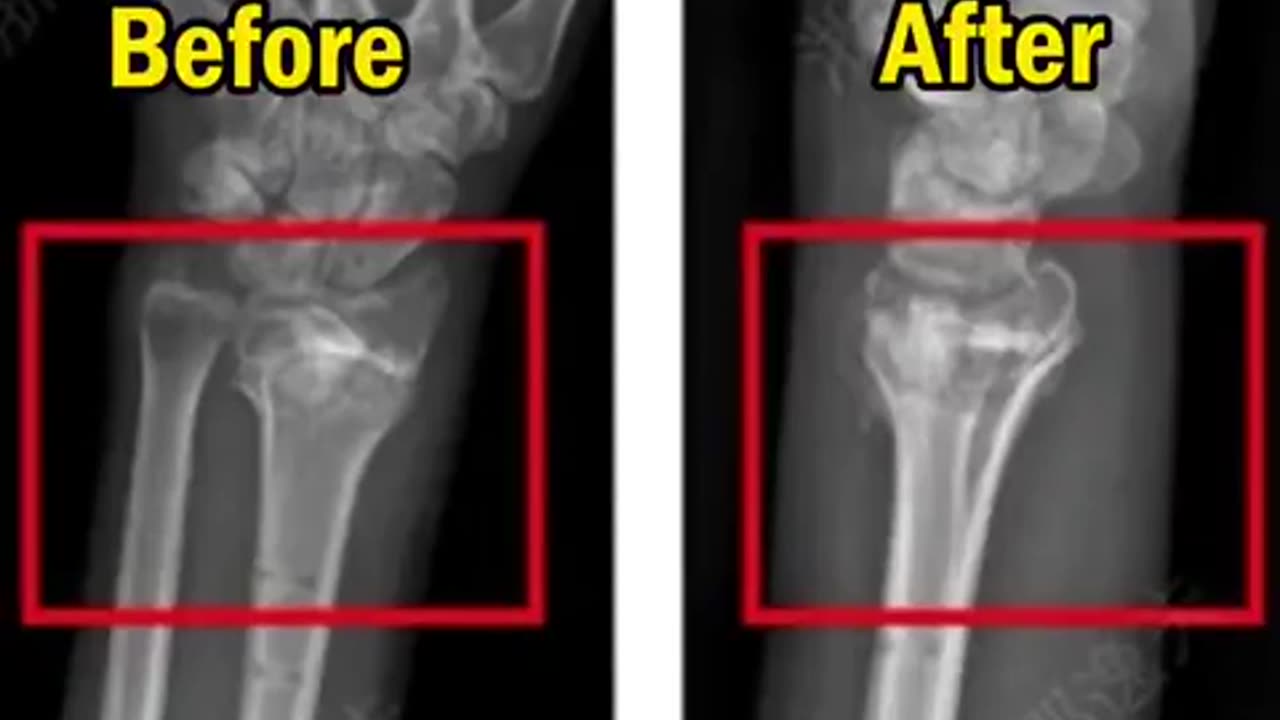

🧠💉 China's First Bone Glue: Faster Healing in 3-5 Minutes! | FeedMyCuriosity

China has revolutionized fracture repair with its first bone glue. This innovative technology can fix shattered bones in just 3-5 minutes, eliminating the need for secondary surgeries. What's the most groundbreaking medical discovery you've heard about? Let us know! 👉 To feed your curiosity with more amazing content, make sure you Like & Subscribe! #Science #Medical #Innovation